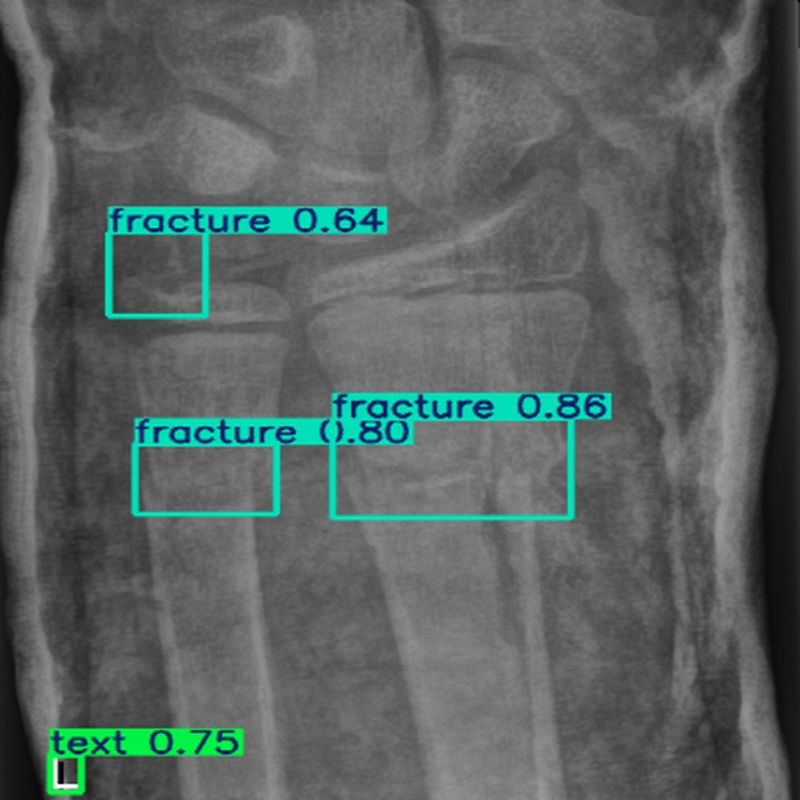

现场环境 在医学成像环境中,使用X射线、CT或MRI等设备获取图像。图像采集过程中可能存在噪声干扰,且骨折目标通常较小,仅占图像像素的2.3%左右,需要在低对比度和复杂背景的条件下进行检测。

使用对象 医学图像中的骨折区域,包括不同类型的骨折(如骨异常、骨损伤等),尤其是小目标骨折区域。

输出数据 骨折检测结果,包括骨折区域的边界框坐标、类别标签(如骨折、金属等)以及置信度。

测试结果 在测试集上,ASC-YOLO模型实现了61.1%的mAP@50,比基线YOLO模型提高了7.4%。断裂类别的mAP@50达到95%,金属类别的mAP@50达到97%。